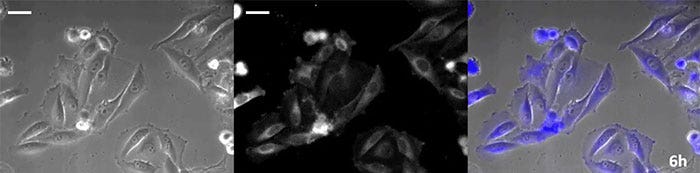

Luciferin vom Coelenterazin-Typ hat eine besonders hohe Leuchtkraft, aber da es in der Zelle innerhalb kurzer Zeit oxidiert, ist eine rechtzeitige Zugabe für Langzeitbeobachtungen unerlässlich. Um dieses Problem zu lösen, haben wir die Zellen mit hochintensivem lumineszierendem Protein perfundiert und das Coelenterazin über ein automatisches Gerät zugegeben, so dass die Lumineszenz kontinuierlich überwacht werden konnte. So konnten wir das Lumineszenzbild in Kombination mit der Phasenkontrast-Bildgebung 24 Stunden lang beobachten (Abbildung 4).

6 Stunden

Abbildung 4-2 6 Stunden